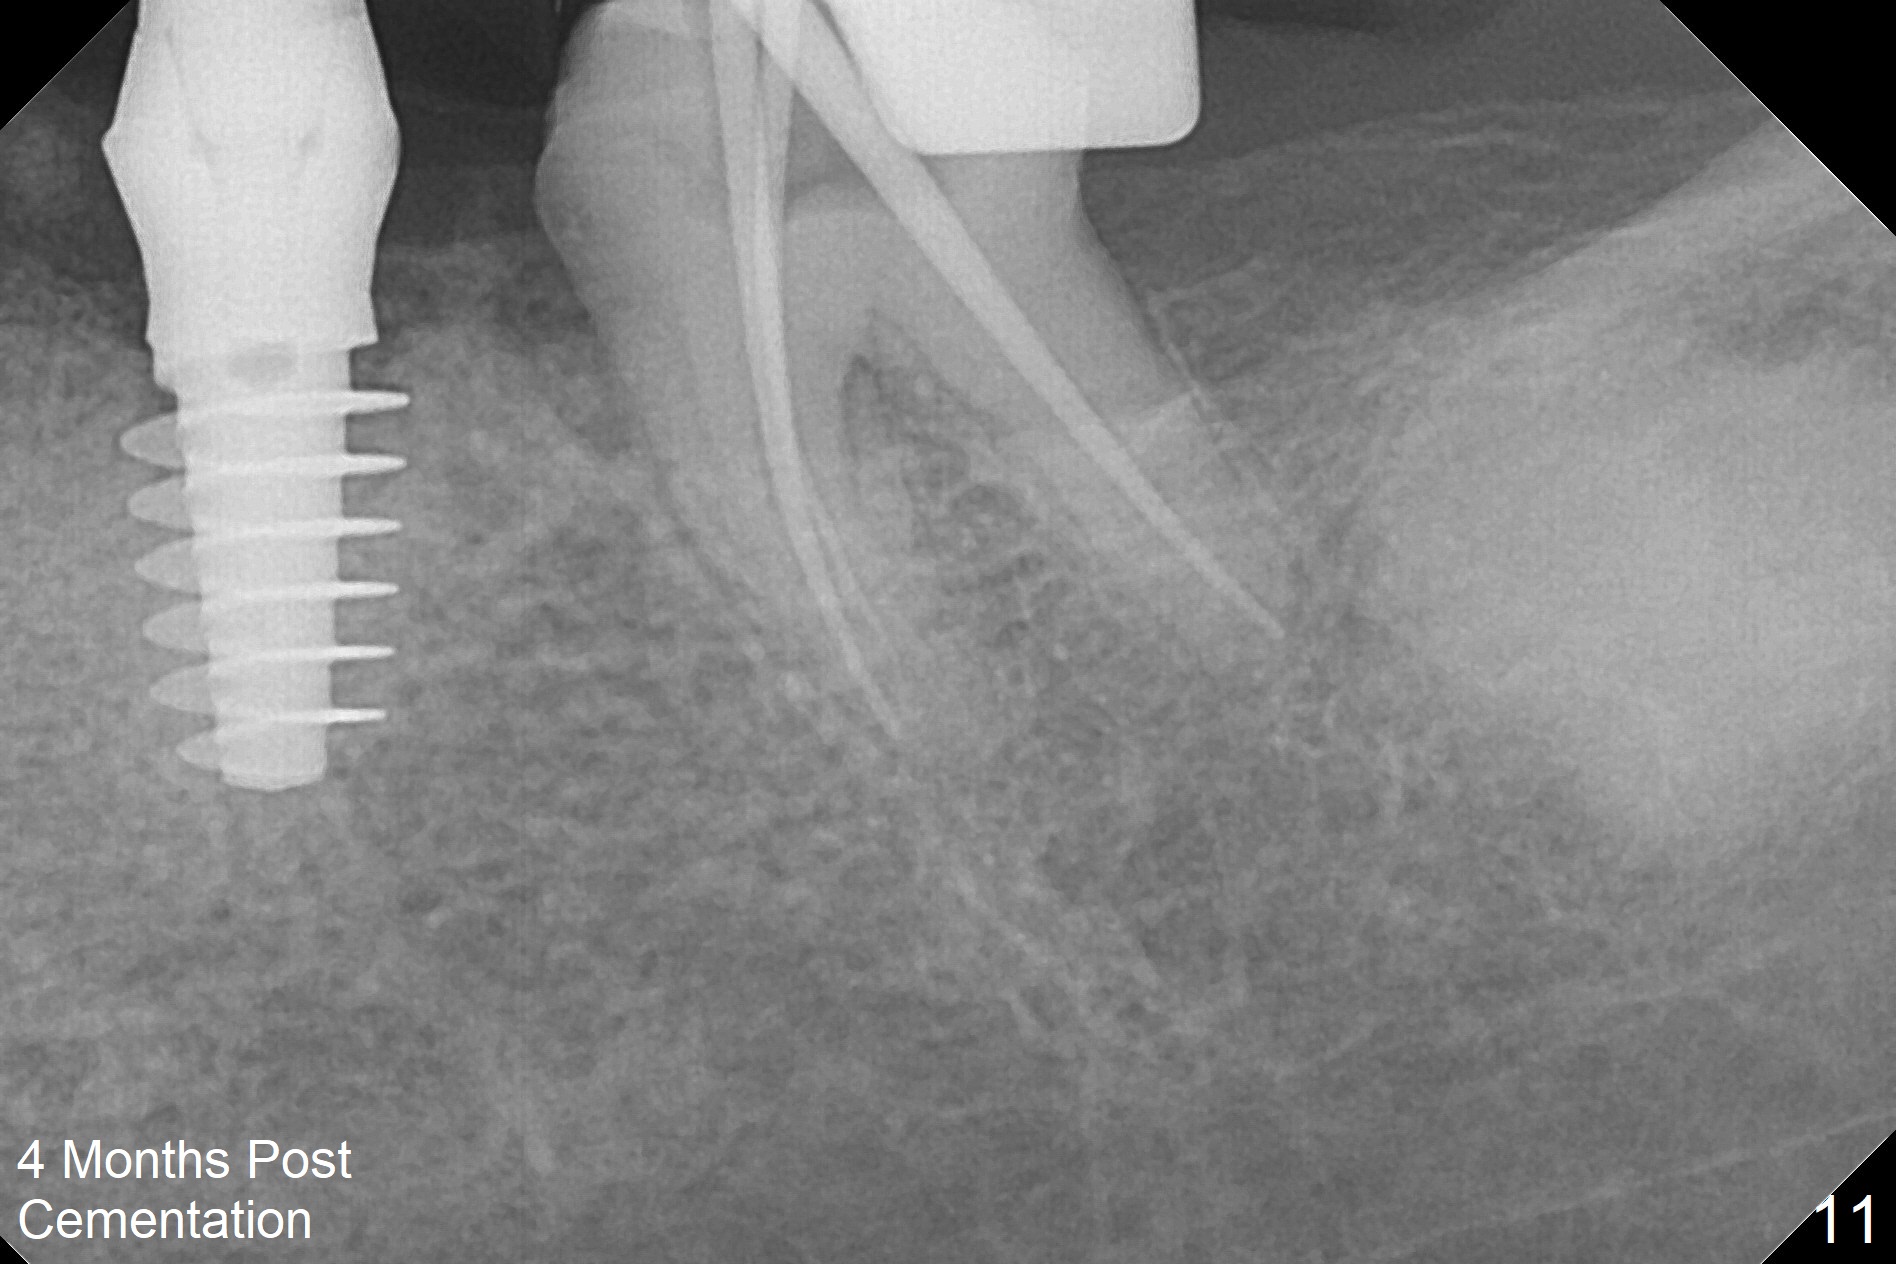

There is no bone loss at #20 or 19 six and 3 months postop, respectively (Fig.6,7). After placing and trimming a 4.3x3 mm Magicore solid abutment, impression is taken (Fig.8). After cementation for #19 and 20 crowns, the crown of #20 is removed for cement removal; attention is paid to cement removal around the crown at #19. In fact, the removal is ineffective with the crown of #20 is reseated and retightened (Fig.9 >). Repeated removal proves to be futile (Fig.10 >). The most effective method will be to take X-ray immediately after #20 crown removal and reseating without torque so that it will be easier to remove the remaining cement if needed. It may be ok in term of hygiene, since proximal brush is used daily. While the crowns at #18 and 19 are being redone because of food impaction, the tooth #18 needs RCT; the Magicore seems to have no bone loss 4 months post cementation (Fig.11). CBCT shows that the Magicore seems to have been placed in the middle of the crest 7 months post cementation (Fig.12 (B: buccal)). The gingiva at #19 is apparently healthy 8 months post cementation. The crown at #19 is recemented 10.5 months post cementation (Fig.13).